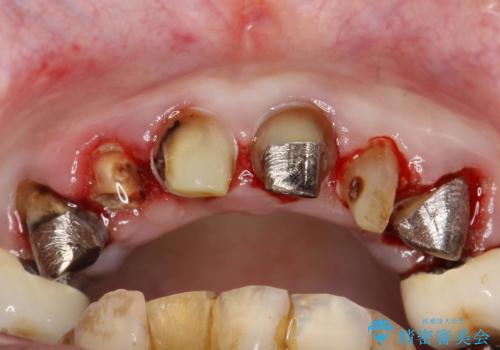

前歯の低クオリティな治療の実態 妥協無い治療で根本からやり治す

・虫歯がとりきれていない

・接触部分がガタガタで適合の悪い金属

・全く無菌の努力がされていない根管治療

など、いい加減な治療は「治療」ではなく、むしろ医原性に歯の寿命を短くします。